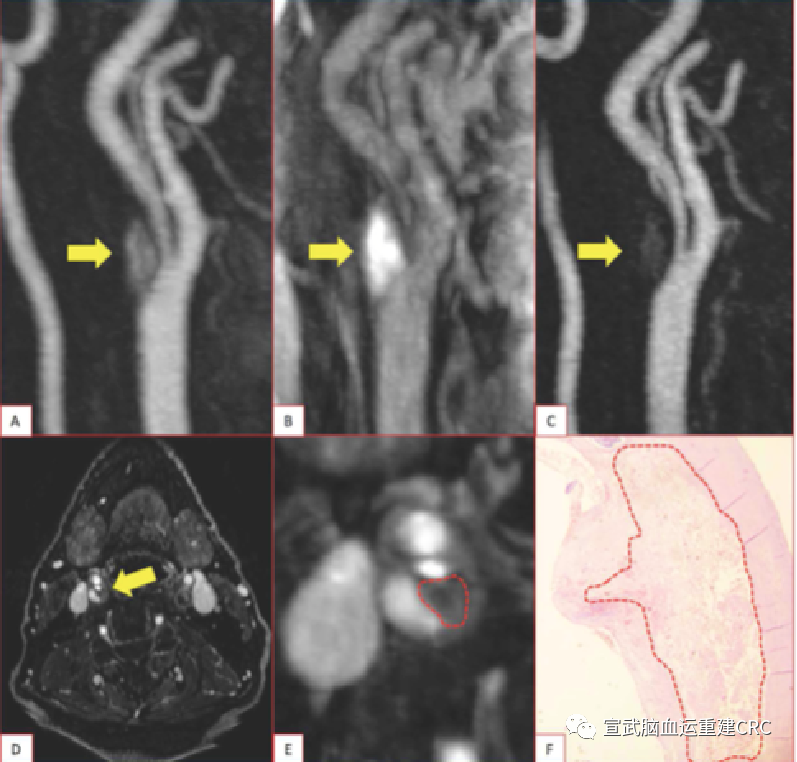

斑块特征 & 临床决策

易损斑块:脂质丰富,薄层纤维帽,斑块内出血,浅层钙化结节,炎症活跃。

如何让支架治疗更加安全有效?在手术前,判断斑块的特点。

现在认为核磁的准确程度最高,且无创。

斑块评价:

颈动脉的TOF-MRA成像中,斑块内高信号与支架术后新发梗死有很明显的相关性。即TOF出现斑块内高信号的病人在支架植入后,围手术期可能更容易出现新发的梗死。

TOF-MRA高信号→易损斑块(IPH)→NILs↑

术前IPH的评估

指导治疗方式选择

预测CAS预后

合并斑块内出血等特征的易损斑块,CAS围术期卒中事件风险高

应用MRI术前评价斑块,易损斑块可以选择CEA,降低CAS风险

术前进行斑块的评价,用TOF去评价。